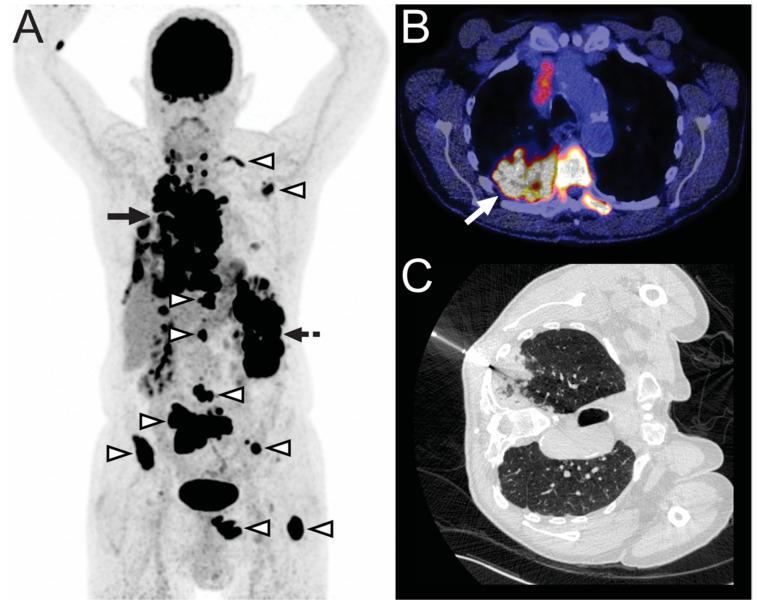

临床及氟代脱氧葡萄糖正电子发射断层扫描/计算机断层扫描(FDG-PET/CT)对恶性疾病的怀疑:活检确认是否仍然必要?

Clinical and FDG-PET/CT Suspicion of Malignant Disease: Is Biopsy Confirmation Still Necessary?

BACKGROUND

Biopsy of F-fluoro-2-deoxy-D-glucose (FDG)-avid lesions suspected for malignancy remains an invasive procedure associated with a variety of risks. It is still unclear if the positive predictive value (PPV) of positron emission tomography (PET)/computed tomography (CT) is sufficiently high to avoid tissue sampling. Therefore, the purpose of this study was to determine the PPV of F-FDG-PET/CT for malignancy in patients with a clinical suspicion of active malignant disease.

METHODS

This single-center retrospective study included 83 patients who had undergone FDG-PET/CT within 60 days before CT- or ultrasonography-guided tissue sampling and whose request form for CT- or US-guided tissue sampling requested mutation analyses. The latter implies a high clinical suspicion of active malignant disease. The nature of each biopsied lesion was determined based on the results of the pathological analysis and/or clinical and imaging follow-up of at least 12 months.

RESULTS

In total, eighty-eight FDG-avid lesions were biopsied. The PPV of FDG-PET/CT for malignancy was 98.9% (95% CI: 93.8-99.8%). For patients with an oncological history, the PPV was 98.7% (95% CI: 92.9-99.8%), and for patients with no oncological history, the PPV was 100% (95% CI: 74.1-100.0%). There was no significant difference between the PPV of the group with and without an oncological history ( = 0.71). In two cases, an unsuspected malignancy was diagnosed.

CONCLUSION

Although the PPV of FDG-PET/CT for malignancy in patients with a clinical suspicion of active malignant disease is high, biopsy remains recommended to avoid inappropriate patient management due the non-negligible chance of dealing with FDG-avid benign disease or unexpected malignancies.